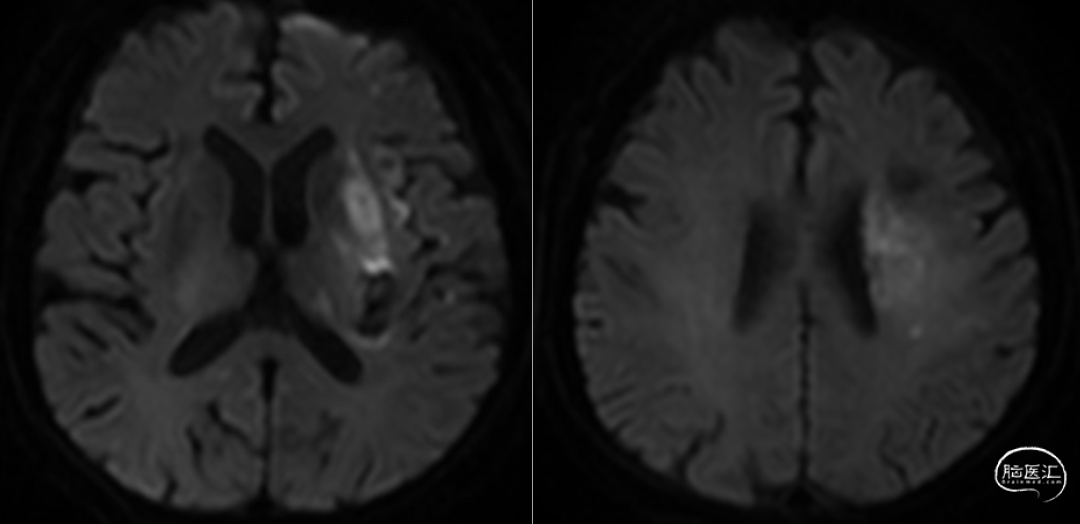

支架取栓配合抽吸一次再通,mTICI分级:3级。观察20分钟后造影左侧大脑中动脉M1段开通良好,血流通畅。DynaCT见左侧基底节区少量造影剂外渗。

术后入NICU治疗,术后第二天,患者右侧上、下肢恢复到4级。术后3天MRI示左侧基底节、脑室旁少量梗死灶,术后一周启动抗凝,达比加群100mg Bid。